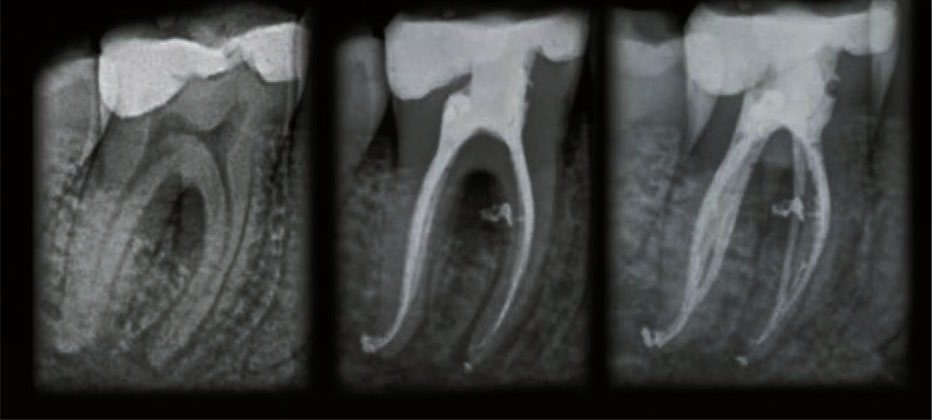

Польза от использования лазера Waterlase iPlus подтверждена уникальным клиническим исследованием в области пародонтологии, соответствующим строгим стандартам AAP Best Evidence Consensus, опубликованным в Journal of Periodontology.

РЕЗУЛЬТАТ: минимально инвазивные протоколы Waterlase REPAIR™ получили не только положительные отзывы пациентов (меньше отеков, гематом и кровоточивости), но и показали более короткое время проведения процедур при клинической эффективности, сопоставимой с современными методами открытых разрезов.